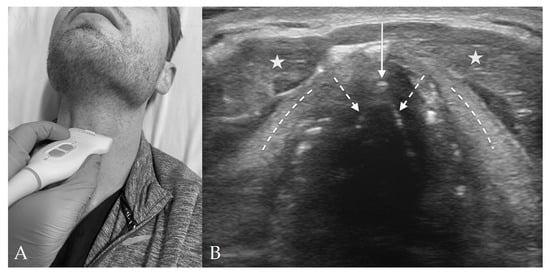

3. Probe Selection and Technique

4. Upper Airway Sono-Anatomy

4.3. Thyroid View

4.4. Cricothyroid View